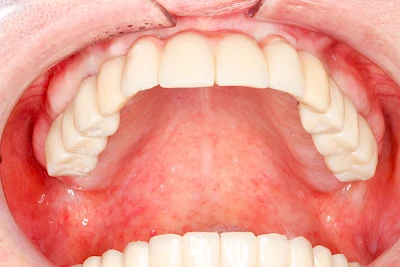

Implantate: Prothesen

Bei herausnehmbaren Prothesen werden Implantate eingesetzt, um den Halt und den Tragekomfort der Prothesen zu verbessern. Dazu kommen verschiedene Verbindungselemente zum Einsatz:

- Teleskope

- Kugelköpfe

- Tellerförmige Lokatoren

- Stege

- Magnete (selten)

Neben rein implantat-getragenen zahnärztlichen Versorgungen werden bei herausnehmbaren Prothesen Implantate auch in Sinne einer "strategischen Pfeilervermehrung" ergänzend zu eigenen Zähnen zur Verankerung eines Zahnersatzes genutzt.